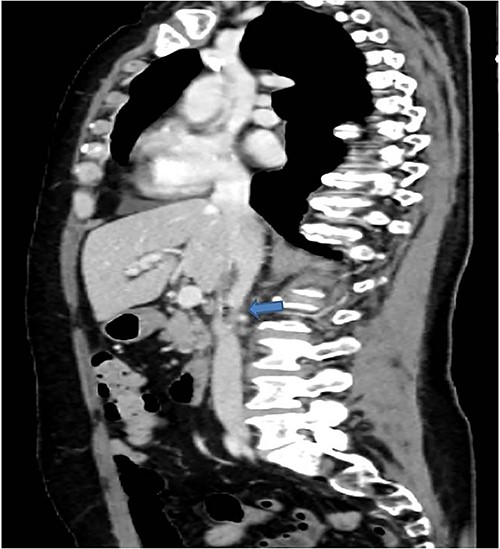

Therefore, given the persistence of the septic state and the radiological findings, the patient underwent laparotomy. Dense retroperitoneal fibrosis surrounded the IVC and the third section of the duodenum (Fig. 3). After complete mobilization of the duodenum with exposure and preparation of the entire subhepatic inferior caval vein and the two renal veins, the duodenal incision located at the level of the posterior wall of its third portion and the caval vein were sutured (Fig. 4). The cholecystectomy with Kehr drainage placement to protect the bowel suture and a jejunostomy were performed.

The intraoperative finding confirms the location DCF at the third duodenal portion.